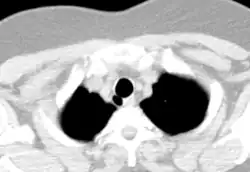

A traquéia de um adulto tem um diâmetro interno de cerca de 1,5 a 2 cm e um comprimento de cerca de 10 a 11 cm, mais larga nos machos do que nas fêmeas.[1] A traqueia começa na borda inferior da cartilagem cricoide da laringe[2] ao nível da sexta vértebra cervical (C6) e termina na carina,[1] o ponto onde a traqueia se ramifica nos brônquios principais esquerdo e direito, ao nível da quarta vértebra torácica (T4),[1] embora a sua posição possa mudar com a respiração.[2] A traquéia é cercada por 16 a 20 anéis de cartilagem hialina ; esses 'anéis' têm 4 milímetros de altura no adulto, incompletos e em forma de C.[1] Os ligamentos conectam os anéis.[2] O músculo traqueal conecta as extremidades dos anéis incompletos e corre ao longo da parede posterior da traqueia.[2] Além disso, a adventícia, que é a camada mais externa de tecido conjuntivo que envolve a cartilagem hialina, contribui para a capacidade da traqueia de dobrar e esticar com o movimento.[3]

Embora a traquéia seja uma estrutura da linha média, ela pode ser deslocada normalmente para a direita pelo arco aórtico.[4]